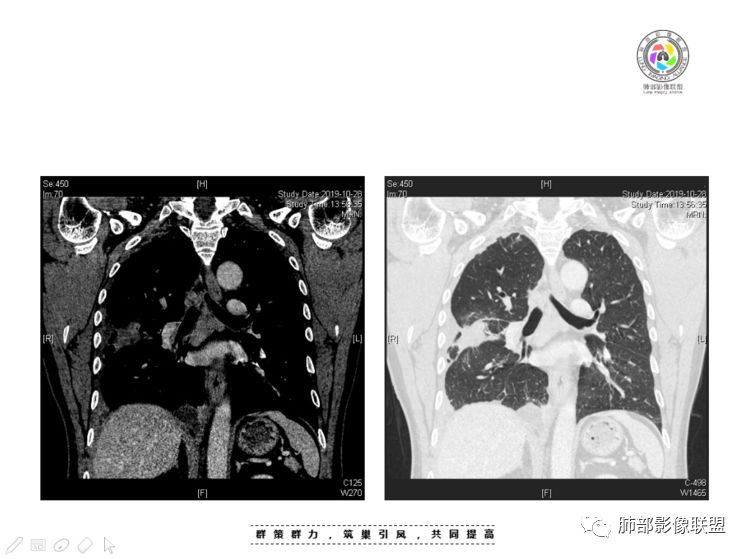

穿越七海的风:右前纵隔占位,恶性肿瘤,生殖来源?右肺实变是占位or肺不张?考虑为部分肺不张FeNo:右前纵隔占位,右肺结节,胸膜凹陷,小尾巴,右肺不张,考虑恶性杨旭华:恶性,前纵隔肿物,与血管关系密切,上腔静脉变窄,右肺野一元论考虑叶间裂增厚,恶性胸膜间皮瘤可能大小丽:到底是纵隔来源还是胸膜来源?我怎么倾向于胸膜来源,和叶间胸膜关系密切,而且纵隔内上腔静脉是向内侧推移。胸膜肿瘤(间皮瘤?SFT?)包裹性胸腔积液?马春平(张家港市一院胸外科):前纵隔占位,左无名受压,右大量胸腔积液可能是胸导管汇入处侵犯受压,考虑纵隔鳞癌孙冰伟:右上纵隔占位,也感觉和叶间胸膜关系密切,右侧胸膜局限性增厚,考虑恶性可能性大灵:前纵隔占位,血性胸水,胸膜凹凸不平,查见肿瘤细胞,结合免疫组化考虑胸腺癌。鉴别胸膜间皮瘤。采莲:右前上纵膈旁可见类圆形肿块,纵隔血管内移,感觉来源于胸膜,肿块内密度低,似水样密度,右侧胸膜广泛增厚,少量胸腔积液。心包少量积液。考虑胸膜间皮瘤,鉴别肺癌并胸膜转移?水晶石头:患者中年男性,胸闷15天。有“高血压、慢性肾小球肾炎”病史。查肿瘤标志物正常,胸水提示渗出液,胸水病理查见瘤细胞。胸部CT:右肺上叶后段结节、斑片影,见胸膜牵拉、包裹积液及部分纤维条索灶,似见卫星灶,右侧胸膜增厚。前纵隔脂肪密度增厚,右侧可见类圆形低密度(液体)肿块,边缘光滑。综合考虑右肺腺癌并胸膜转移,结核可能。周太狼:考虑纵隔胸膜来源肿瘤,恶性,胸膜间皮瘤伴转移?徐飞:中年男性,影像为右侧胸腔及叶间积液,叶间胸膜增厚轻度强化。前纵隔右侧心缘旁团块,可见坏死。胸水见癌细胞,综合考虑恶性,胸腺癌伴转移。小赵:中年男性,血性胸水,常规查见癌细胞,李凡他实验阳性。胸部CT示前纵隔见不均匀密度影,与邻近大血管分界不清,囊变坏死明显,增强扫描呈不均匀强化,心包及右侧胸膜增厚,并心包及右侧胸腔少量积液。综合考虑胸腺癌。右肺中叶病变周围见多发纤维条索,支气管部分进入病灶,考虑炎性病变。流心明智:患者,男性,50岁。胸闷15天。高血压20年,慢性肾小球肾炎15年。肿标正常,胸水提示渗出液,胸水查见癌细胞。胸部CT:右肺肿块影,斑片影,索条影,可见胸膜牵拉、多发包裹积液,纵隔上腔静脉受累,心包受累。综合考虑:ROSE似腺?考虑右肺腺癌并胸膜转移,心包受累。鉴别胸腺Ca、淋巴瘤,纵隔病变不懂,等老师们精彩分析。王秀仙:前纵膈囊实性肿块,与纵膈分界不清,心脏大血管及上腔静脉受压向内后移,右侧后胸膜、侧胸膜增厚,右侧叶间裂不规则增厚,心包积液,根据腔静脉移位情况,考虑纵膈胸膜来源恶性肿瘤,胸膜间皮瘤?鉴别胸腺癌并胸膜转移。高广飞:上纵隔占位,右侧叶间胸腔积液,需考虑恶性自信人生:多发囊实性病灶,包裹性积液,考虑胸膜来源 只是没有看到壁结节,恶性胸膜间皮瘤巴伟:前上纵隔占位,胸膜及心包结节,考虑胸腺瘤或癌,右肺病灶,先考虑陈旧炎性病变。Lenle董:前纵隔占位,部分边缘模糊,病灶内囊变?坏死?上腔静脉受侵,考虑胸腺癌;叶间片状影,强化明显,炎性考虑。常志强:前纵隔囊实混杂密度肿块,边界不清,实性部分强化明显,结合胸水内见癌细胞,考虑恶性肿瘤伴转移。飞鹰行动:前纵隔占位,软组织密度及囊性密度,实性部分密度均匀,致密,病灶与周围血管分界不清,增强后病灶强化有类似不温不火强化,部分血管受侵犯,右肺见肿块样病变及条索状病变,一元论,考虑淋巴瘤,二元论,考虑胸腺瘤B2—B3伴右肺病变。尽量一元论考虑,淋巴瘤可能。看图说话:右肺索条病灶,边缘膨隆,胸膜牵拉,考虑右肺癌伴胸膜转移。晨:前纵隔囊实性肿块,与纵隔分界不清,右侧后胸膜、侧胸膜增厚,右侧叶间裂不规则增厚,考虑纵隔胸膜来源恶性肿瘤,考虑胸腺癌并胸膜转移。丽:中年男性,前纵隔囊实性肿块,呈偏心性生长,临近大血管受压推移,增强后实性部分不均匀强化,心包可见条形积液,考虑胸膜来源恶性肿瘤,胸腺癌可能大。另右肺多发斑片状高密度影及实变密度影,实变影呈均匀强化,右侧胸膜局限性增厚,考虑炎性病变。小飞:右前纵隔囊实性占位,实性部分明显强化,右侧叶间胸膜增厚,右侧胸腔积液,心包积液,考虑恶性胸腺瘤!尘缘:支持恶性胸腺瘤(囊实性肿块,实性强化,且侵犯纵隔,脂肪间隙模糊)伴肺内及胸膜转移。浪迹天涯:考虑侵袭性胸腺瘤——胸腺前纵隔占位,周围脂肪间隙模糊不清。尘缘:不除外另一种可能:二元,肺内腺癌合并胸膜转移,纵隔的畸胎瘤可能。一米阳光:晨读中年男性,右肺结节影,叶间裂及胸膜增厚牵拉,右侧胸水。心包多发结节改变。胸水查见癌细胞。考虑,腺癌并转移。鉴别,胸膜间皮瘤并转移前纵隔囊实性占位,二元考虑。心灵鸡汤:老年男性,右肺中叶外段长条状软组织密度影,边缘膨隆,邻近胸膜牵拉,部分胸膜有栽脏,右中叶外侧段支气管堵塞,常规考虑恶性肿瘤,腺癌可能,结核、鳞癌不除外,另右肺上叶斑片影,小叶性肺不张?右前纵隔囊实性不规则形密度影,其内见部分脂肪样极低密度影,与邻近血管边界不清,心包外膜有侵犯,增强未见纵隔窗平扫,实性及分隔见增化,其内低密度影未强化,考虑低度恶性纵隔肿瘤,间皮瘤可能,畸胎瘤、淋巴瘤待排,建议支气管镜及穿刺活检。曹志勇:右前纵隔考虑来源于胸膜的恶性肿瘤,右肺内病灶考虑鳞癌,二元德芙~云味:中年男性,右肺见结节、斑片影,右侧包裹积液、胸膜牵拉,纤维条索,前纵隔囊性占位,考虑腺癌、并转移。欧阳英:右前中纵隔囊实性肿块及右肺内结节灶,支持恶性肿瘤,胸腺癌并肺内转移可能张延军:前纵隔见不规则软组织影,密度不均,右侧缘见囊变区,纵膈及侧胸壁胸膜增厚,增强呈不均匀强化,右肺中叶见结节灶,近段支气管阻塞,叶间胸膜不规则增厚,考虑1:右肺中叶腺癌伴纵膈及胸膜转移;2:前纵膈侵袭性胸腺瘤并胸膜侵犯,中叶炎性改变?彭君:老年,前纵隔占位 ,坏死边缘清, 侵犯心包 右侧胸膜及叶间胸膜结节 ,少量胸水, cea不高 ,考虑恶性, 间皮瘤可能 ,转移待除外。毛勤香:恶性没问题,胸水查见癌细胞,一元还是2元,右肺中叶肿块,边缘毛糙,局部似有毛刺,周围有粘连,右侧胸膜腔少量积液,胸膜增厚多发结节,含叶间裂结节,纵膈脂肪间隙模糊,纵膈胸膜增厚,心包增厚积液,右前那个类圆形低密度肿块,纵膈血管内移,我考虑胸膜来源可能性大,综合考虑,一元肺腺癌并多发转移,二元考虑胸膜间皮瘤并多发转移,肺内炎症不张。

本例纵隔与肺内两处病变,回顾总结分析:

1、右肺内病灶,病灶呈结节样,边缘欠规则,局部膨隆,叶间裂胸膜牵拉凹陷,再看相应支气管腔堵塞截断,临床资料胸水中查到癌细胞,均提示病灶倾向恶性,腺癌的病理意见与之相吻合。

黄勇老师总结,腺癌如果与胸膜、叶间裂紧贴或伴胸膜凹陷,胸膜、叶间裂多发结节,应当高度怀疑腺癌转移。

2、前纵隔内病灶囊实性混杂密度病灶,囊性病灶主要位于右侧,张力较高,有分隔影,囊壁右侧缘光整,病灶左侧实性部分边界不清明显强化,病灶肺瘤交界面大部分边界清楚,部分模糊。

胸腺瘤/胸腺癌:病灶内那么大的囊,常规考虑B型以上胸腺瘤,囊内有分隔影,病灶周围脂肪间隙模糊,常规考虑侵袭性胸腺瘤或胸腺癌,若侵袭性胸腺瘤,常侵犯胸膜、心包,很少累及肺。胸腺癌易侵犯胸膜、肺并纵隔淋巴结及远处转移。但肺内腺癌形态更符合原发灶。胸膜及叶间裂转移则即可来自肺,也可来自胸腺癌。

尽管前纵隔病灶缺乏相关病理资料,但是小编还是认为肺内与纵隔病灶以二元论解释。只是肺内恶性病灶引发的胸膜改变可能会影响我们对纵隔病灶的判断。